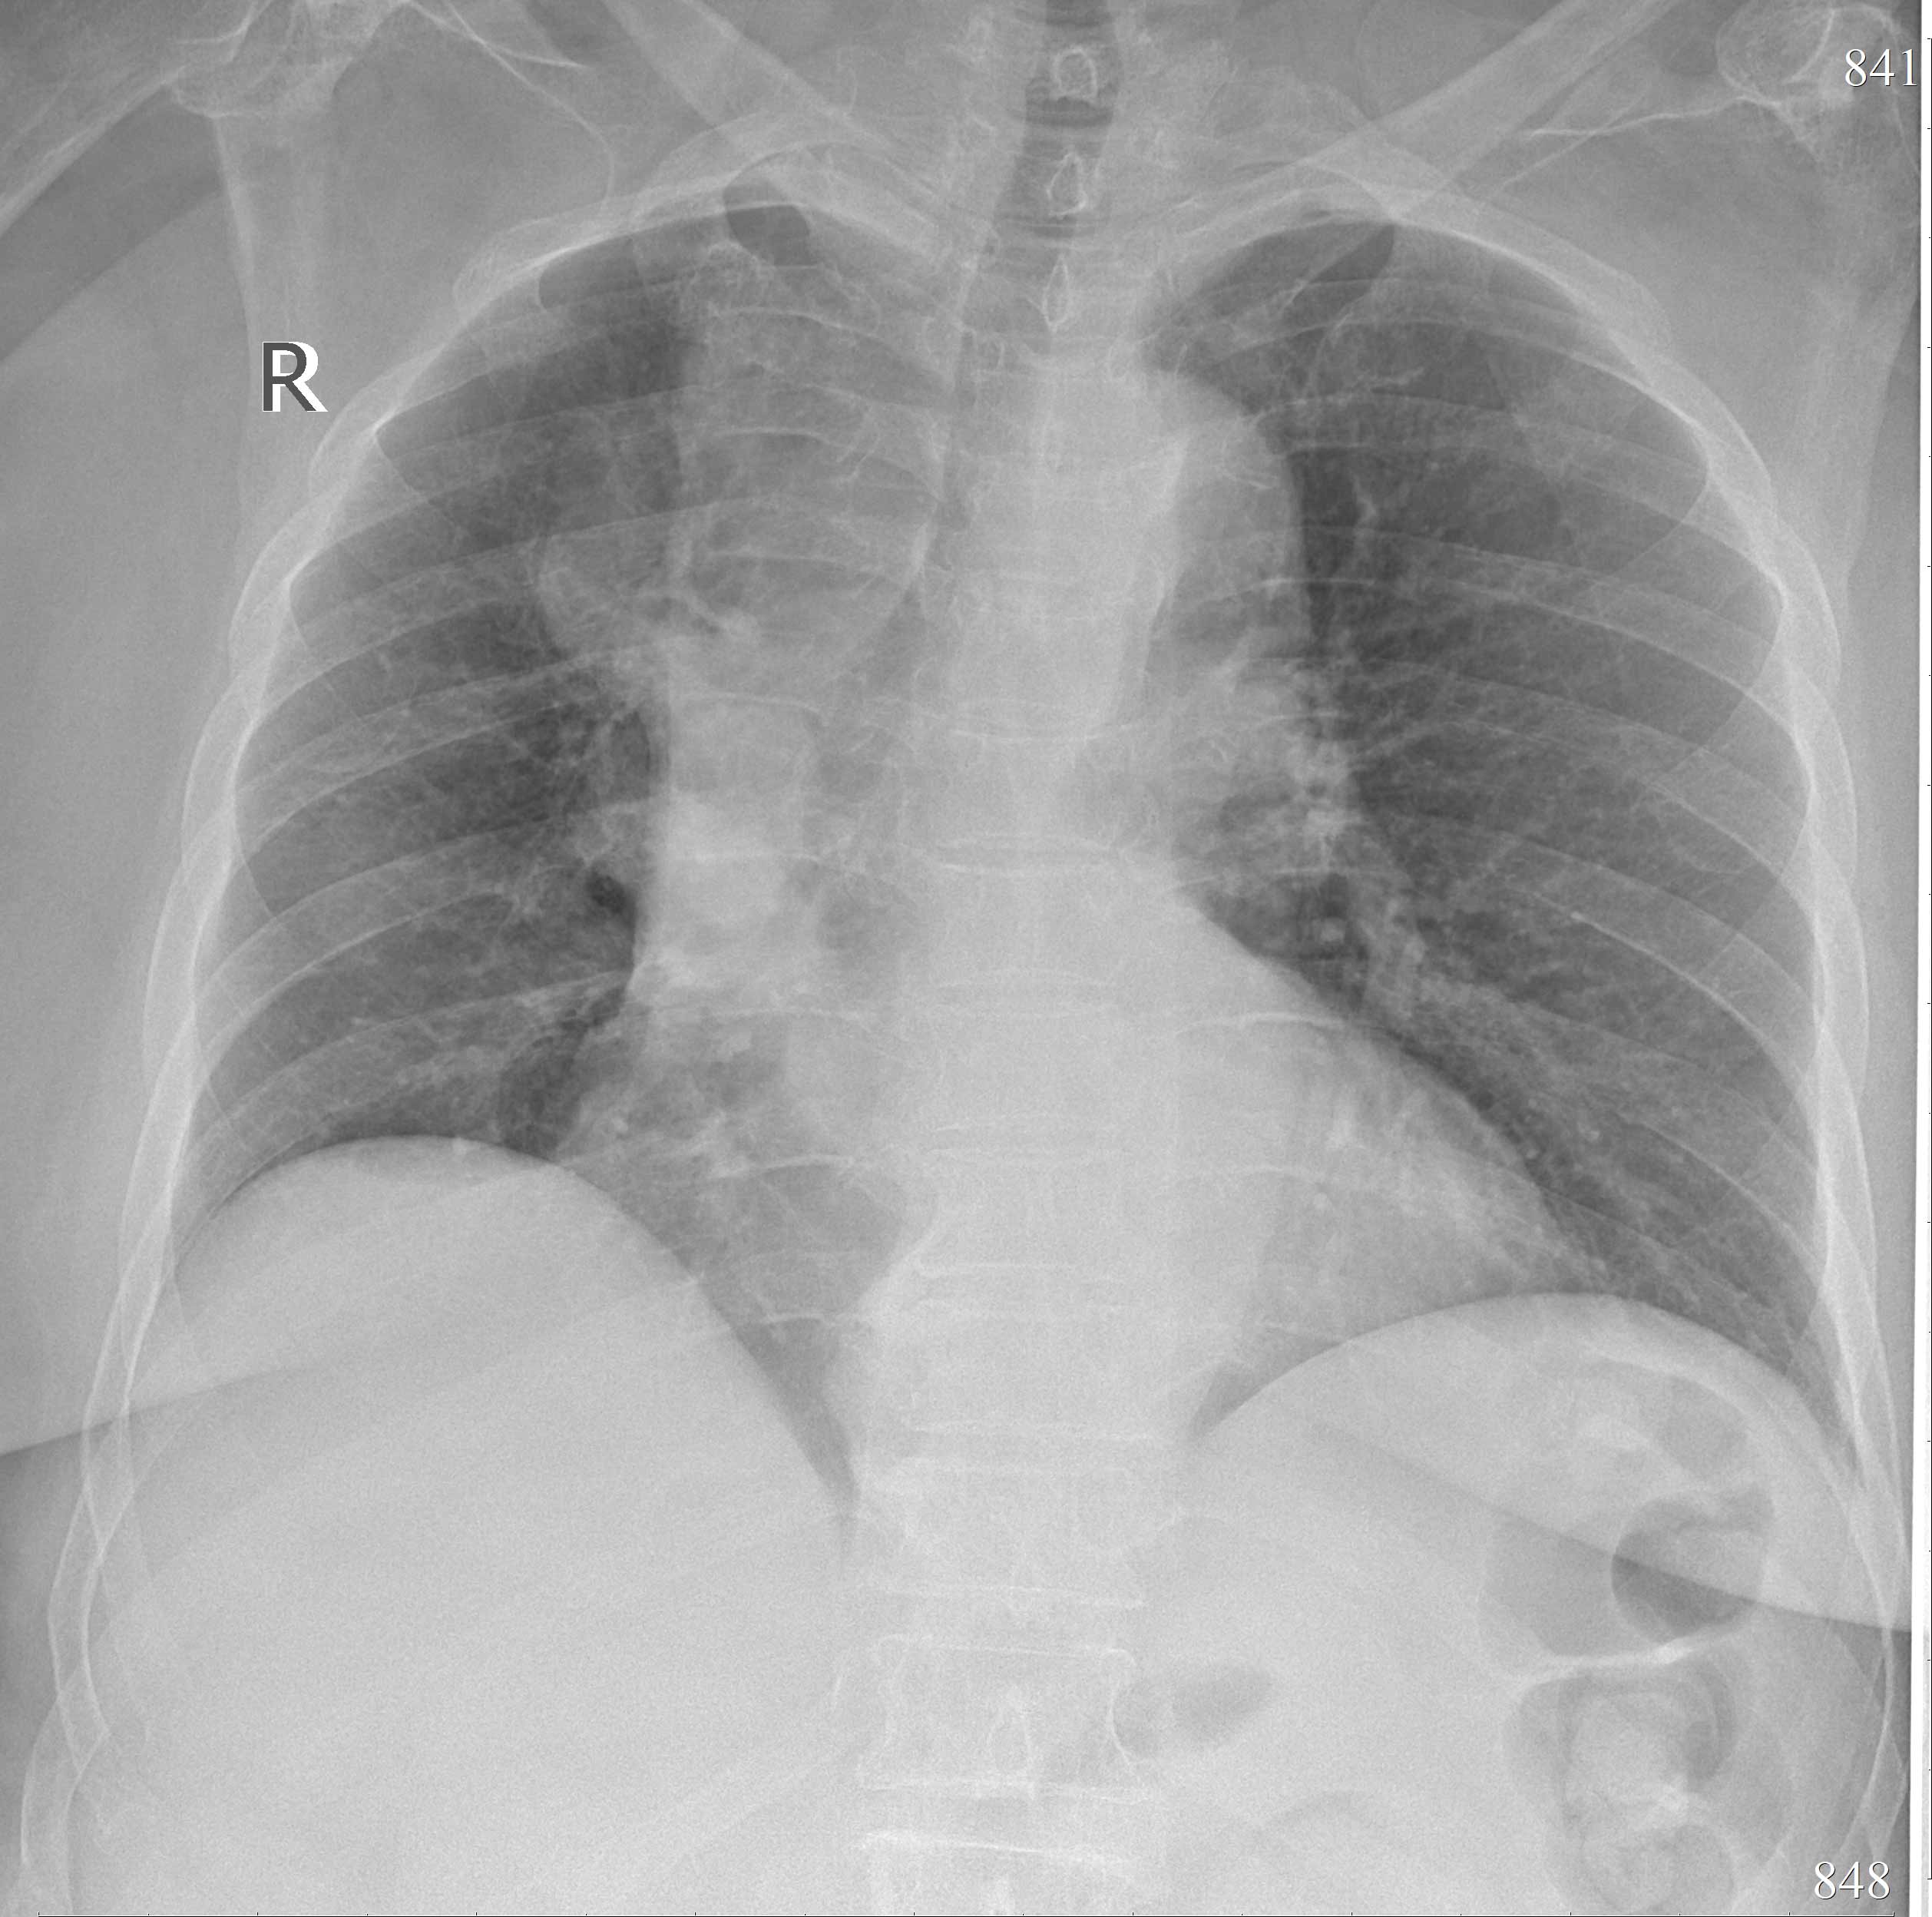

Описан основанный на высокочастотной фильтрации и морфологической обработке изображения метод обработки микрофокусных рентгеновских снимков, повышающий контраст деталей рентгенограммы. Одной из наиболее информативных методик рентгенографии является микрофокусная рентгенография. В ряде случаев микрофокусные рентгеновские изображения не могут быть достоверно проанализированы из-за особенностей способа съемки. Так, основными недостатками микрофокусных рентгеновских изображений чаще всего являются неравномерный фон, искаженные яркостные характеристики и наличие шумов. Предлагаемый метод повышения контраста мелких деталей изображения основан на идее сочетания высокочастотной фильтрации и морфологической обработки изображений. Метод состоит из следующих шагов: подавление шумов на изображении, высокочастотная фильтрация, морфологическая обработка изображения, получение результирующего изображения. В результате применения метода усиливается яркость контуров на изображении. На полученном изображении все объекты будут иметь двойные контуры. Метод был апробирован при обработке 50 рентгенограмм органов грудной клетки пациентов с разнообразной патологией. Рентгенограммы были выполнены в городской Мариинской больнице Санкт-Петербурга на цифровых стационарных и передвижных рентгеновских аппаратах. На большей части рентгенограмм удалось улучшить контраст снимков, выделить границы объектов. Также метод был применен в микрофокусной рентгеновской томографии для улучшения информативности проекционных данных и улучшения восстановления 3D-образа объекта исследования. Как для первого, так и для второго случаев метод показал удовлетворительные результаты. Разработанный метод позволяет существенно повысить информативность микрофокусных рентгеновских снимков. Полученные практические результаты позволяют рассчитывать на широкие перспективы применения метода, особенно в микрофокусной рентгенографии.

1. Рентгеновский снимок грудной клетки после обработки | |

Описан основанный на высокочастотной фильтрации и морфологической обработке изображения метод обработки микрофокусных рентгеновских снимков, повышающий контраст деталей рентгенограммы. Метод состоит из следующих шагов: подавление шумов на изображении, высокочастотная фильтрация, морфологическая обработка изображения, получение результирующего изображения. На полученном изображении все объеns имеют двойные контуры. Метод был апробирован при обработке 50 рентгенограмм органов грудной клетки пациентов с разнообразной патологией.